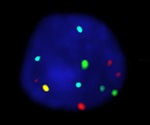

Oxford Gene Technology launches Cytocell FISH probe for bladder cancer